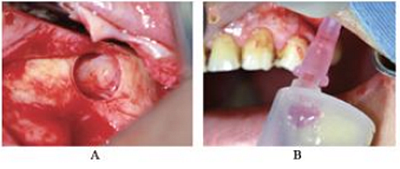

CBCT示:上頜竇內(nèi)見液平面約達(dá)竇腔1/3(考慮為沖洗液未吸干凈),上頜竇垂直高度得到補足,26牙高度8.4mm,27牙高度為9.5mm(圖3)?;颊呔芙^穿刺液送病理檢查。

圖3 上頜竇外提升術(shù)后CBCT。

注:A,矢狀面;B,26頰舌向切面;C,27頰舌向切面;D,28頰舌向切面。

術(shù)后5個月,患者無流涕、鼻塞,無其他自覺癥狀。CBCT示:左側(cè)鼻甲基本恢復(fù)正常,上頜竇高密度影較前明顯減少,仍有少量黏膜增厚。26牙RBH8.1mm,27牙RBH8.4mm(圖4)。擬26~28牙種植修復(fù)。

圖4 種植前CBCT。注:A,矢狀面;B,26頰舌向切面;C,27頰舌向切面;D,28頰舌向切面。